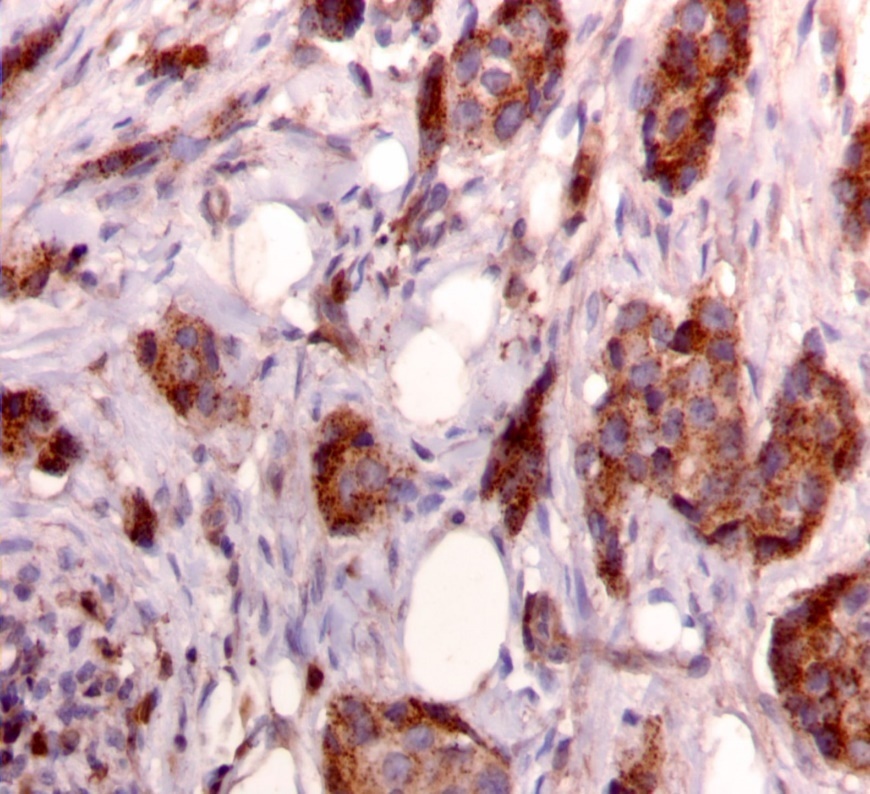

We used the following histologic criteria for IRS-1 and IRS-2 staining patterns which are outlined in a previous study.13 For IRS-1, a nuclear pattern was defined as diffuse nuclear staining (Figure 1). IRS-2 staining patterns were defined using the following criteria: Diffuse cytoplasmic staining was defined as evenly distributed cytoplasmic reactivity (Figure 2); punctate cytoplasmic staining was defined as clearly demarcated puncta of staining within the cytoplasm (Figure 3); and membrane staining was defined as focal or diffuse membranous staining (Figure 4). Sections of normal pancreas and normal breast tissue were used for positive and negative controls. The pathologists assessing staining patterns were blinded to the tumor recurrence score and all other data at the time of assessment.

Figure 3.Punctate cytoplasmic staining pattern for IRS-2. (IRS-2 immunohistochemical stain, 200x magnification)